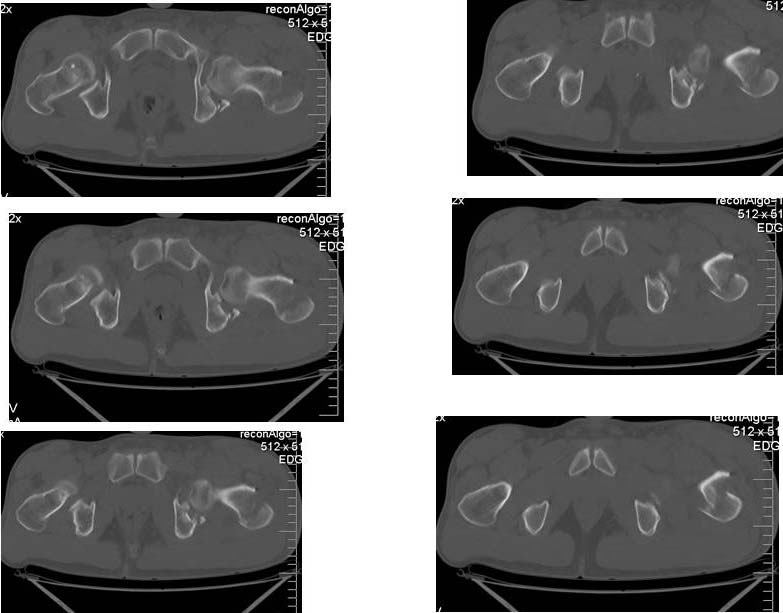

Коллеги! Хотелось бы посоветоваться по тактике лечения больного.Больной 24 лет, травму получил катаясь на горных лыжах. На рентгенограммах вертельный перелом. Но при детальном изучении снимков появилось подозрение на перелом головки бедра. Это побудило выполнить КТ. На КТ перелом заднего края вертлужной впадины.Планируем проксимальный стержень. А вот с вертлужной впадиной вопрос. Синтезировать или консервативно. "За операцию" внутрисуставной перелом, с вдавлением фрагмента суставной поверхности. "Против" смещенный фрагмент в задне-нижнем квадранте и в меньшей степени нагружаем... С ув Коробушкин Г.

Трактовка "в меньшей степени нагружаем" не очень правильная, потому что топографически "задний край" находится выше и является основным удержателем головки от вывиха. При малых размерах перелома, иногда можно обойтись без операции, но решение принимается после доказательных рентген исследований Evaluation Under Anesthesia. Потом любая импрессия суставной поверхности - показание к оперативному вмещательству!

Доступ классический Kocher-Langenbeck, который позволит из одного доступа зафиксировать перелом вертлужной впадины и чрезвертельный перелом бедра. При этом варианте вопрос фиксатора для бедра не имеет значения, подойдет любая пластина для проксимального бедра или гвоздь!